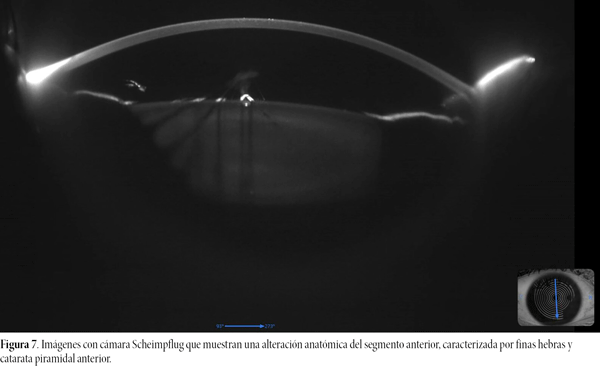

La agudeza visual del ojo derecho sin corrección previa a la cirugía correspondía a LogMAR 1,33. Al examen con refractometría reveló una agudeza visual mejor corregida de LogMAR 0,1 y una refracción de -5,75 D esfera y -1,00 D cilindro a 12° (OI, cilindro -0,50 a 165°). Los estudios prequirúrgicos —incluidos análisis de respuesta ocular (fig. 4), evaluación de ojo seco (fig. 5), topografía corneal y paquimetría (fig. 6)— se hallaron dentro de parámetros normales. La cámara Scheimpflug mostró alteración anatómica del segmento anterior, caracterizadas por las hebras y la catarata piramidal (fig. 7). Además se realizó una tomografía óptica de coherencia siendo el de papila normal pero en el estudio macular se observó un pucker parafoveal sin edema (fig. 8).

Figura 7. Imágenes con cámara Scheimpflug que muestran una alteración anatómica del segmento anterior, caracterizada por finas hebras y catarata piramidal anterior.